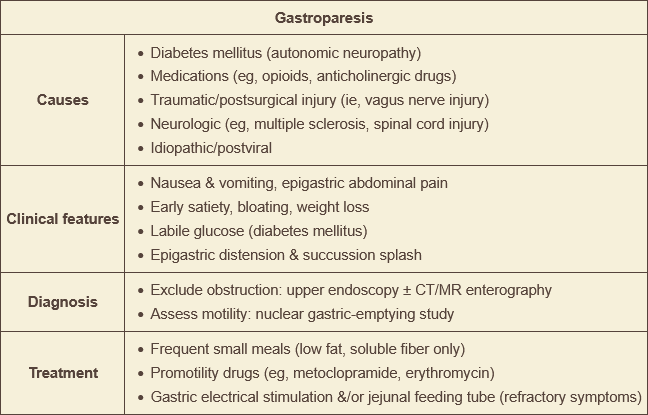

treat gastroparesis with…

metoclopramide